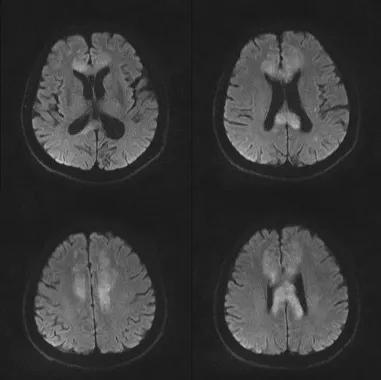

原发性胼胝体变性急性期:T2WI矢状位(A)清晰观察到弥漫胼胝体病变,FLAIR呈高信号(B),DWI呈高信号(C),ADC图呈低信号。

胼胝体压部病变及多发皮层对称性病变,表现为扩散受限